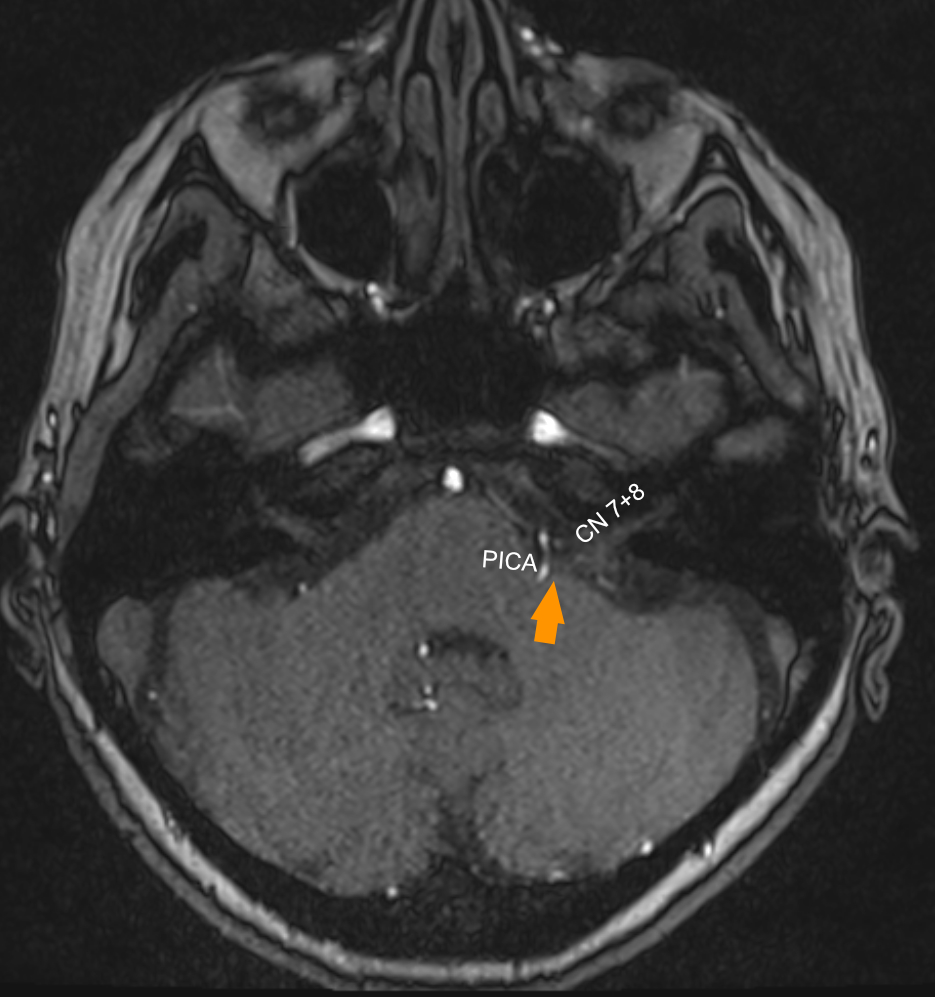

Bildgebung

Neurovaskuläre Konflikte sind häufig schwer eindeutig auf einer MRT Bildgebung zu diagnostizieren. Optimal eignen sich eine TOF und CISS Sequenz zur Beurteilung der Root Exit Zone (REZ) des Nervus facialis.